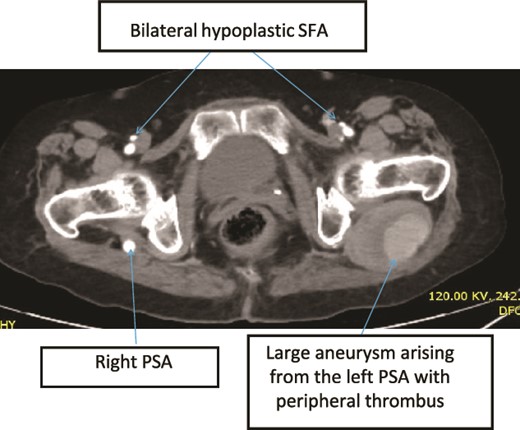

Case 2—axial images of LL CTA of the bilateral LL arteries at the level of the femoral head showing large bilateral PSAs and a large aneurysm with surrounding thrombus of the right PSA.

Case 3—axial images of LL CTA of the bilateral LL arteries at the level of the CFA bifurcation showing large bilateral PSA and small bilateral SFA; large aneurysm with surrounding thrombus at the left PSA.